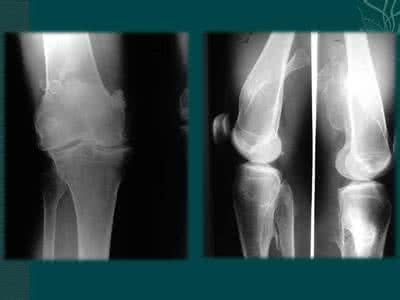

骨肿瘤的临床表现

2.肿胀或肿块

位于骨膜下或表浅的肿瘤出现较早,可触及骨膨胀变形。如肿瘤穿破到骨外,可产生固定的软组织肿块,表面光滑或者凹凸不平。

5.畸形

因肿瘤影响肢体骨骼的发育及坚固性而合并畸形,以下肢为明显。

6.病理性骨折

肿瘤部位只要有轻微外力就易引起骨折,骨折部位肿胀疼痛剧烈,脊椎病理性骨折常合并截瘫。